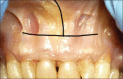

The containment of the elevator muscle of the upper lip and wing of nose was used for the treatment of patients with gummy smile. This technique had corrected esthetic alterations of smile, reducing the upper lip elevation, which results in a smaller gingival display. An upper lip lengthening as well as a reduction in the upper lip shortening when the patient smiled could be observed. The high smile line was corrected without compromising the labial harmony. This study presents an innovative and effective therapeutic option to obtain a natural and harmonious smile. The patient expressed a high degree of satisfaction.